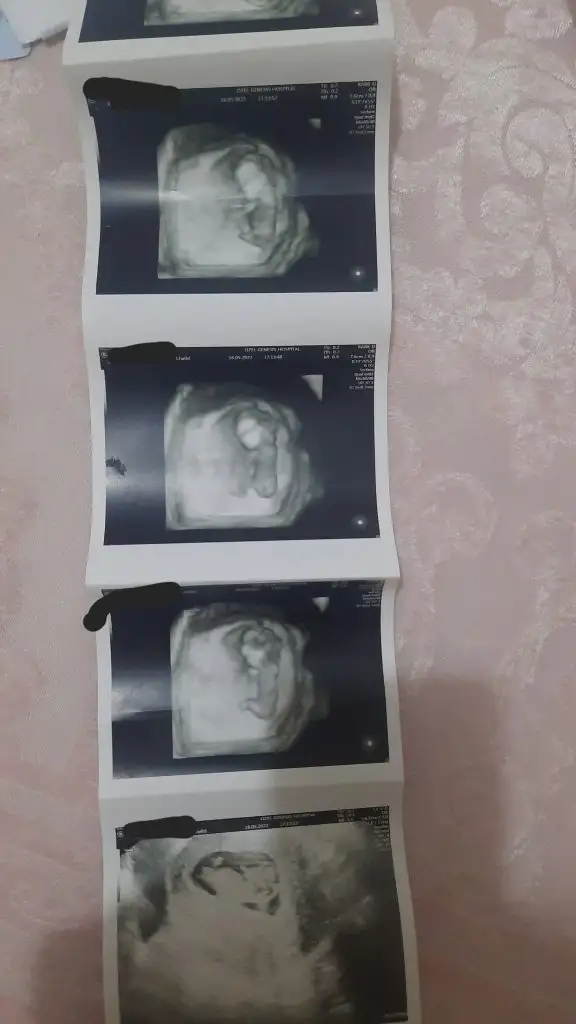

Kiz dedin cnm 16 haftalık oldu ama daha belli degil atiyim yıne ben eski ultrasonucanım 6 haftadayken ne dedim bilmiyorum ama burda paşa gibi

kesen maşallah yuvarlak kız gibi duruyormuş ama paşa benceKiz dedin cnm 16 haftalık oldu ama daha belli degil atiyim yıne ben eski ultrasonu

Hayırlısı cinsiyet daha belli değil çoğu kişi kiz diyor benim içinden kiz geçiyor oglum var onun hareketleri erken başladı bu hic varlığı yok gibi üstüne sürekli ekşi acı seyler tatlıdan uzağım şekerli çay dahi midemi bulandırıyor insallah ilk dediğinin tutar tabi erkek kiz fark etmez ama oğlum var birde kizim olsa insalllahkesen maşallah yuvarlak kız gibi duruyormuş ama paşa bence